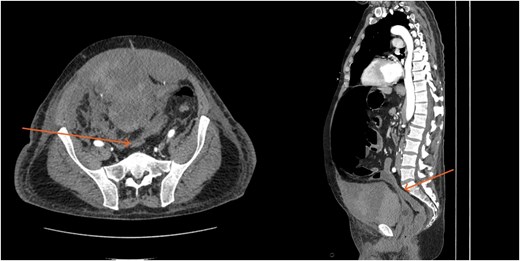

By hospital day 6, the patient’s condition improved. He was weaned from mechanical ventilation, his renal function improved (creatinine declined to 0.7 mg/dl), and hemoglobin stabilized at 8.4 gm/dl. The patient was clinically stable, and on hospital day 8, he was set up for discharge to a rehabilitation institution. However, on this day, he developed generalized abdominal pain associated with tachycardia, pulse = 118, and leukocytosis (white blood cells = 14.8 × 109/l). Physical exam revealed a distended abdomen with diffuse tenderness and sluggish intestinal sounds. A CT scan showed a large volume of pneumoperitoneum, minimal free fluid, and mildly dilated small bowel loops, consistent with a hollow viscus perforation with no identifiable source of perforation (Fig. 5) and a compression of rectosigmoid region against sacral promontory by the enlarged hematoma (Fig. 6). The right colon was decompressed compared with the prior study, and the RSH size remained unchanged, but there was progression of VTE burden. Prior to the acute deterioration, the patient had intermittently reported mild abdominal discomfort, which was initially attributed to the known RSH. There were no clinical signs suggestive of bowel obstruction, such as vomiting or significant abdominal distension. While the patient noted some degree of constipation, he reported that this was consistent with his baseline bowel habits and did not raise concern for new pathology.

CT scan demonstrating compression of large bowel (arrows) by the enlarged hematoma.